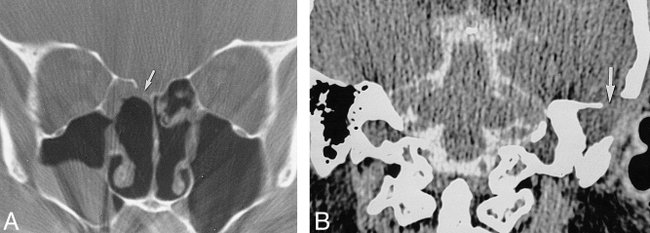

Patient with a defect revealed by CT and a leak revealed by radionuclide cisternography but not by CT cisternography.

A, Radionuclide cisternogram of the head, anterior planar view, shows an abnormal accumulation of radionuclide (arrow) in the left mastoid region.

B, Coronal CT scan of the temporal bone shows a defect (arrow) in the tegmen tympani with adjacent mucosal thickening. The bone and dural defect were confirmed at surgery.

Patient with a bone defect revealed by CT and a leak evident by CT cisternography but not by radionuclide cisternography.

A, Coronal CT scan of the face shows a large defect (straight arrow) in the right cribriform plate with adjacent mucosal thickening. Nasal pledgets can be seen within the nasal cavity (curved arrow).

B, Coronal CT cisternogram of the same region shows accumulation of contrast medium at the defect and extending into the ethmoidal sinus (arrow). The results of radionuclide cisternography and nasal pledgets were normal. There was no surgical confirmation.